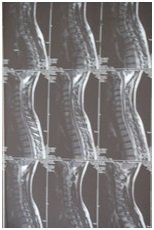

Die Wirbelsäule ist ein Stützorgan unseres Körpers und muss zeitgleich grösstmögliche Stabilität und Mobilität sicherstellen. Die Lendenwirbelsäule ist auch bei alltäglichen Anforderungen enormen Belastungen ausgesetzt. Die Wirbelsäule besteht aus den Wirbelkörpern und den dazwischen liegenden Bandscheiben. Die Bandscheiben sind prallelastisch und dienen als Pufferfunktion. Mit zunehmenden Alter nimmt die Elastizität zunehmend ab.

Bei einem so genannten Bandscheibenvorfall kommt es zum Austritt von Bandscheibengewebe in den Rückenmarkskanal. Dieses ausgetretene Bandscheibengewebe kann so stark auf den Rückenmarkskanal drücken, dass es zu Sensibilitätsausfällen, Lähmungen und Reflexausfällen kommt. Dies stellt oft einen akuten Notfall dar, der sofort behandelt werden muss.

Meist jedoch drückt das Bandscheibengewebe nur leicht auf den Rückenmarkskanal und der Patient nimmt dies als Schmerz war. Dies nennt man eine Bandscheibenprotrusion. Durch den ständigen Druck kommt es zur Entzündung des gesamten Bereiches und die Schmerzen verstärken sich. Die Behandlung dieser Entzündung ist die wichtigste Maßnahme bei der Behandlung. Durch Medikamente (Entzündungshemmer) soll die Entzündung reduziert werden. Dadurch wird der Schmerz leichter oder verschwindet oft gänzlich. Die Behandlung kann sich von wenigen Tagen bis zu mehreren Wochen hinziehen.